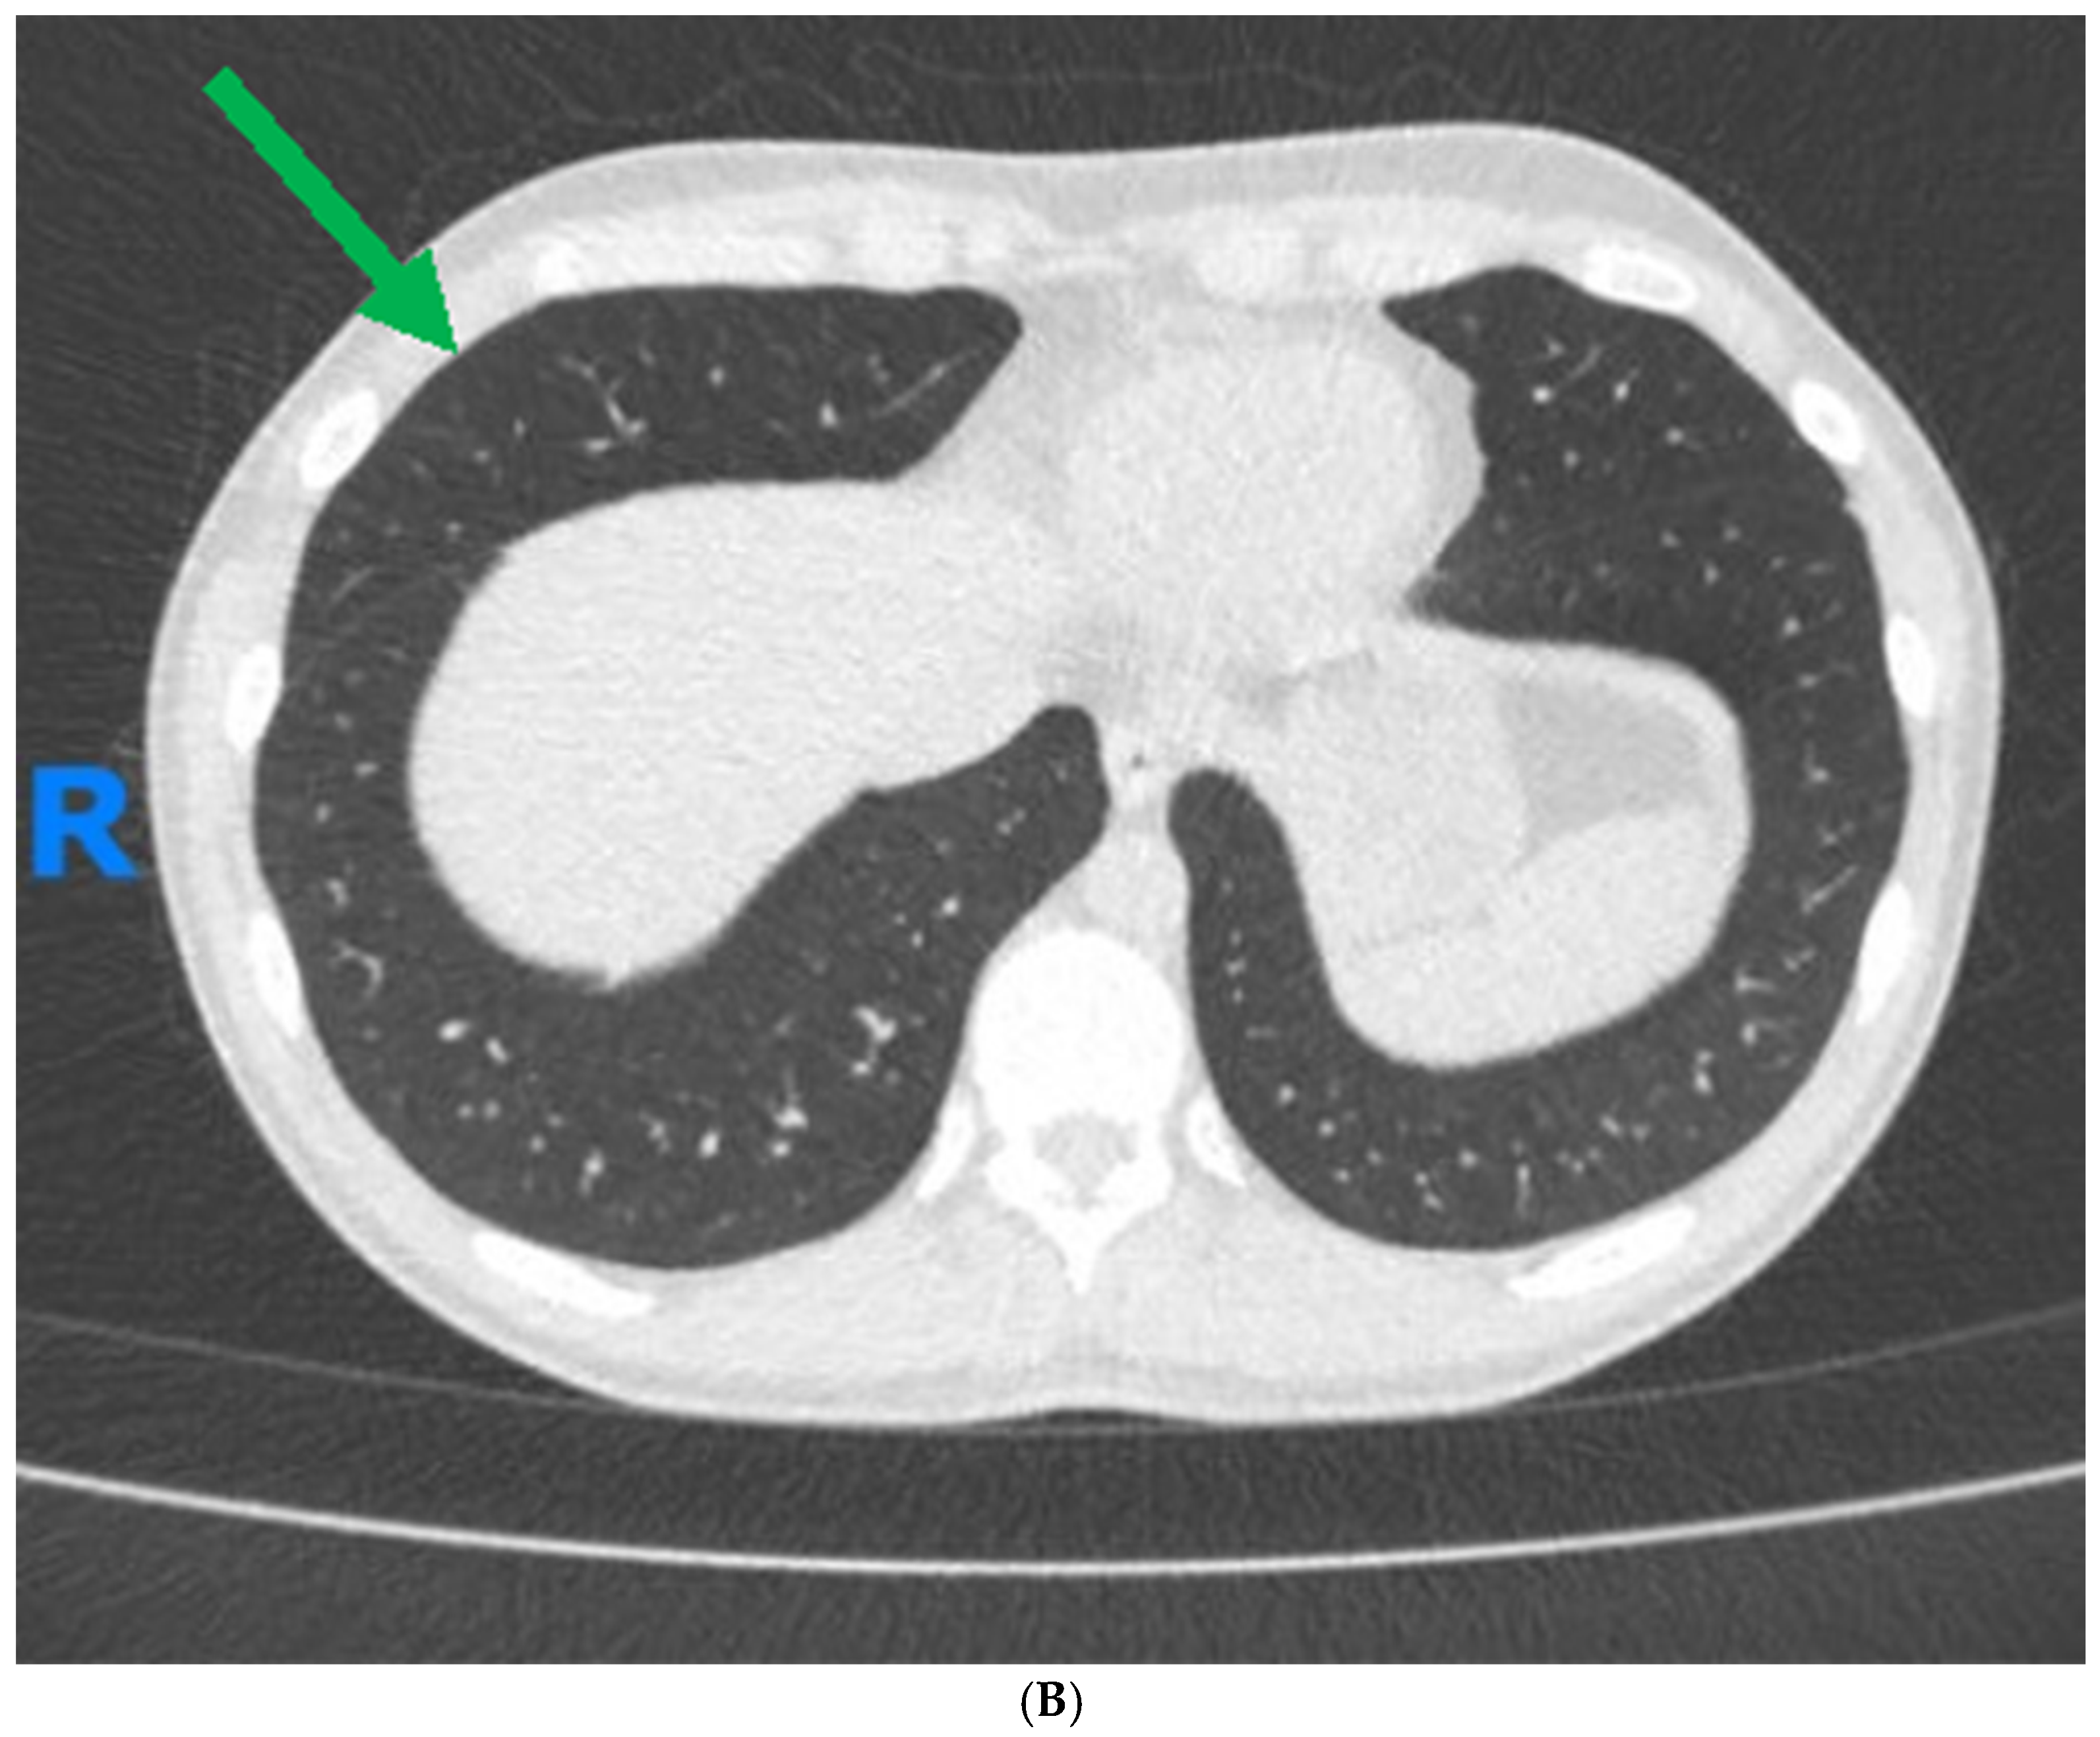

1. Case Report

- Suzuki, A.; Noro, R.; Omori, J.; Terasaki, Y.; Tanaka, T.; Fujita, K.; Takano, N.; Sakurai, Y.; Suga, M.; Hayashi, A.; et al. Pulmonary manifestation of inflammatory bowel disease: Two case reports. Respir. Med. Case Rep. 2023, 45, 101914. [Google Scholar] [CrossRef]